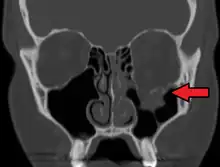

| An orbital blowout fracture of the floor of the left orbit. | |

An orbital blowout fracture is a traumatic deformity of the orbital floor or medial wall that typically results from the impact of a blunt object larger than the orbital aperture, or eye socket.[1] Most commonly this results in a herniation of orbital contents through the orbital fractures.[1] The proximity of maxillary and ethmoidal sinus increases the susceptibility of the floor and medial wall for the orbital blowout fracture in these anatomical sites.[2] Most commonly, the inferior orbital wall, or the floor, is likely to collapse, because the bones of the roof and lateral walls are robust.[2] Although the bone forming the medial wall is the thinnest, it is buttressed by the bone separating the ethmoidal air cells.[2] The comparatively thin bone of the floor of the orbit and roof of the maxillary sinus has no support and so the inferior wall collapses mostly. Therefore, medial wall blowout fractures are the second-most common, and superior wall, or roof and lateral wall, blowout fractures are uncommon and rare, respectively. They are characterized by double vision, sunken ocular globes, and loss of sensation of the cheek and upper gums from infraorbital nerve injury.[3]

Imaging

Thin cut (2-3mm) CT scan with axial and coronal view is the optimal study of choice for orbital fractures.[16][17]